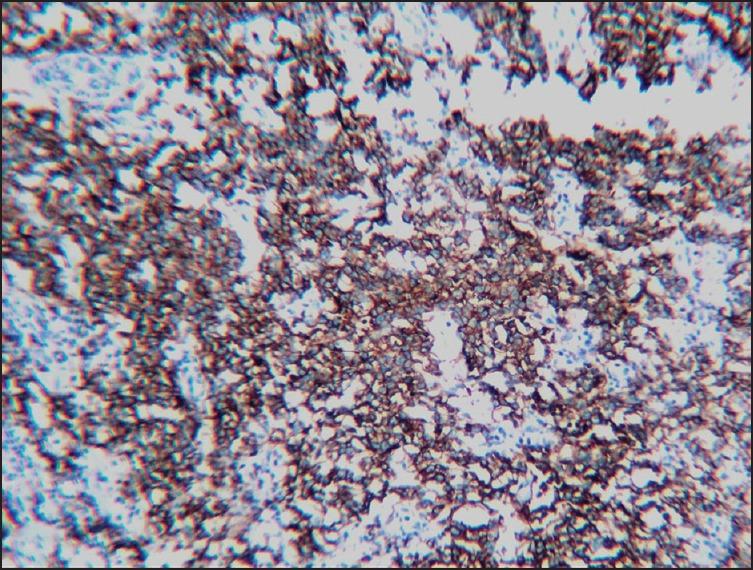

A 22-year-old male patient underwent a segmental resection of the ileum due to clinical symptoms of bowel obstruction and radiological evidence of ileal wall thickening and enlarged mesenteric nodes. Histopathological examination of the resected specimen revealed an extranodal marginal zone B-cell lymphoma(MALToma) of the intestine and tuberculous lesions along with a solitary Peutz-Jeghers polyp. The case is presented for its rarity and to stress upon the clinical and radiological challenges that arise when lymphomas and tuberculous lesions co-exist at the same site.

一名22岁男性患者因肠梗阻临床症状以及回肠壁增厚和肠系膜淋巴结肿大的影像学证据,接受了回肠节段性切除术。切除标本的组织病理学检查显示为肠道结外边缘区B细胞淋巴瘤(黏膜相关淋巴组织淋巴瘤)、结核病变以及一个孤立的黑斑息肉病息肉。该病例因其罕见性以及强调淋巴瘤和结核病变在同一部位共存时出现的临床和影像学挑战而被呈现。